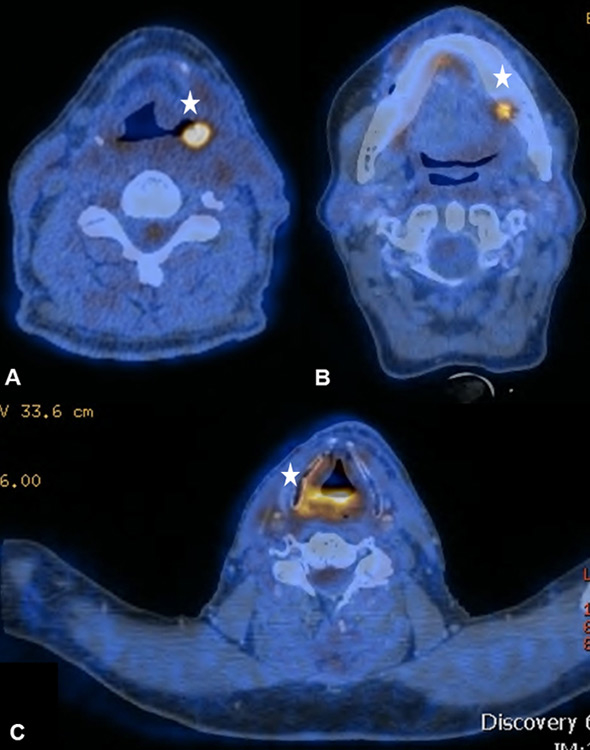

Figure 5

(A) Increased focal uptake in the right submandibular gland in a 54-year old patient, who underwent surgical resection and reconstruction with a pedicled flap owing to a lateral tongue carcinoma. (B) The corresponding T1–weighted magnetic resonance imaging helps to delineate the shifted submandibular gland due to the pectoralis maior myocutaneous flap. (C) Sixty-six year old patient after segmental mandibular resection, mandibular reconstruction and implantation of dental implants due to an anterior floor-of-mouth carcinoma

Typical post-surgical findings were inflammatory FDG uptake of the tongue and the oral cavity due to transoral surgical resections or a shifted submandibular gland owing to a pectoralis major myocutaneous flap (fig. 5AB). Patients after laryngectomy, formation of a tracheostoma and insertion of voice prosthesis frequently showed increased FDG-activity around the voice prosthesis (fig. 6AB). Implantation of synthetic materials in the head and neck region, such as a voice prosthesis, can cause increased mucus production and tracheal wall damage with accompanying immunological cell accumulation and then increased FDG uptake [31]. Lastly, dental implants or non-removable bridgework can also cause artefacts in PET-CT [32]. However, as it was previously shown by our group, those artefacts might partly be reduced in PET-MRI [11, 33]. Therefore, PET-MRI seems to be an additional tool to complement PET-CT, especially when evaluating the oropharynx and oral cavity, since synthetic material typically causes artefacts in this region.